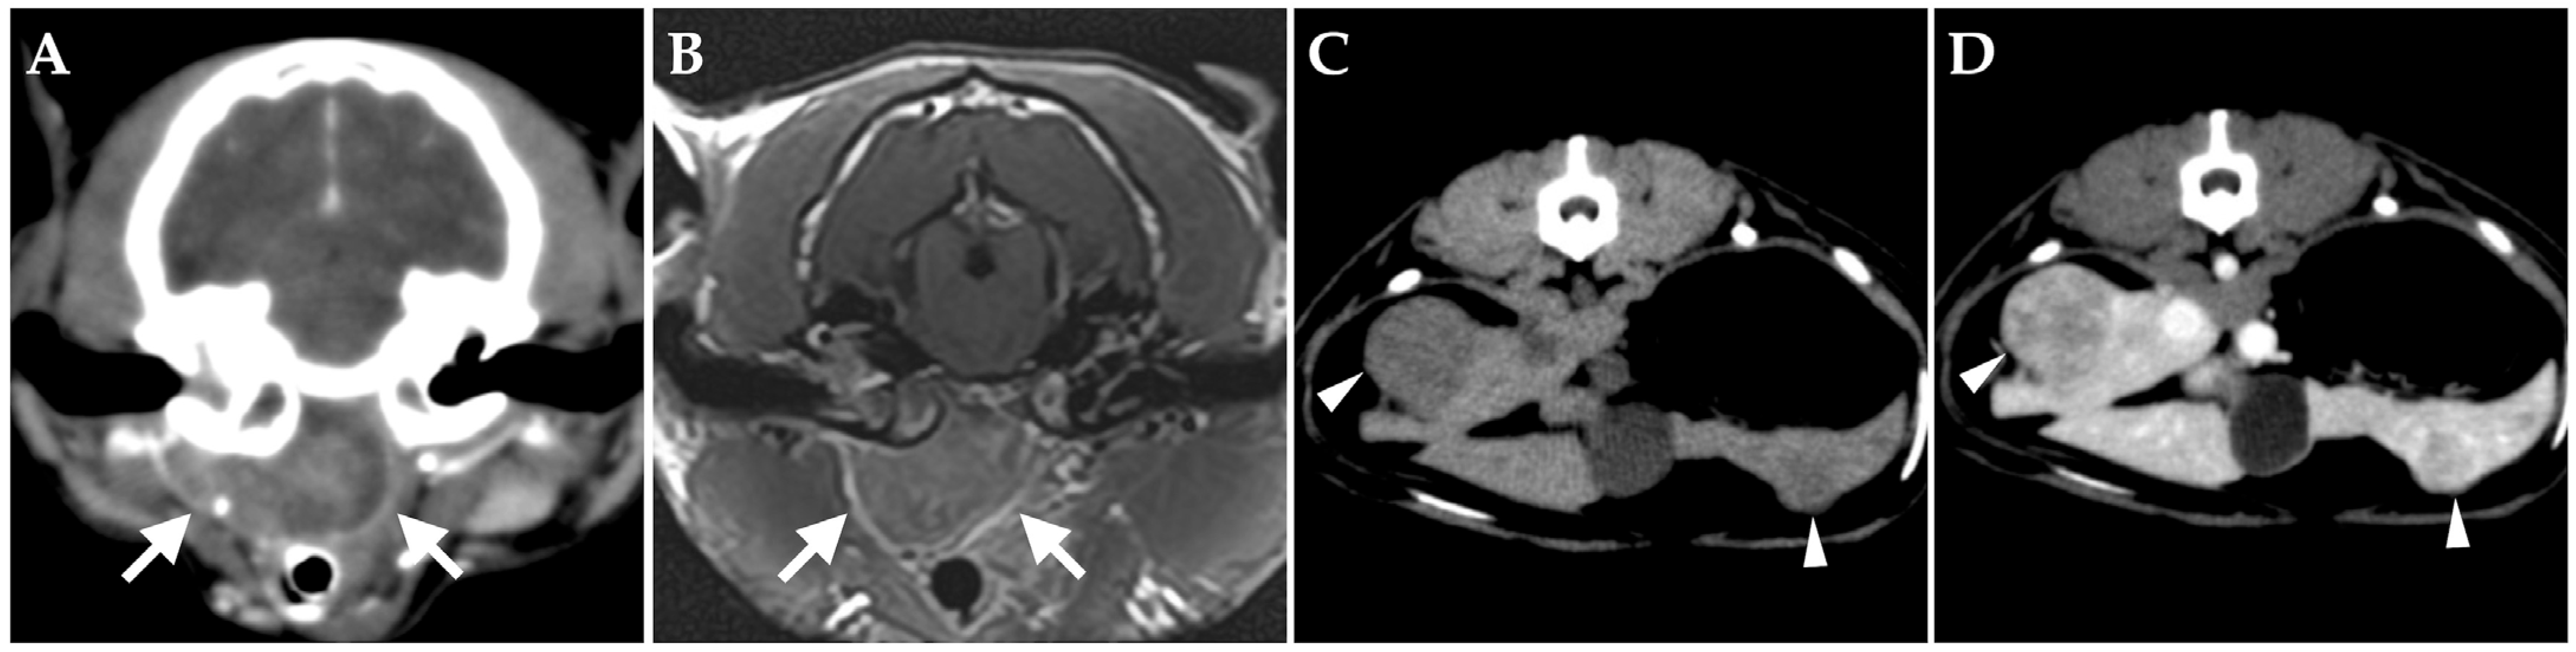

On day 176, the patient developed an unstable appetite and nasal obstruction sounds. Intraoral examination revealed swelling of the soft palate. Blood tests revealed no particular abnormalities. Contrast-enhanced whole-body CT under anesthesia showed unchanged filling of bilateral tympanic bullae and no obvious bony abnormalities. A mass lesion with heterogeneous contrast enhancement was found on the ventral side of the right tympanic bulla, almost completely obstructing the nasopharyngeal passage (Figure 4A). The right medial retropharyngeal lymph node was contiguous with the ventral lesion of the tympanic bulla and showed heterogeneous contrast enhancement. Multiple contrast-enhanced mass lesions were noted in the liver (maximum diameter, 18 mm) (Figure 4C,D). No obvious intrathoracic or intra-abdominal organ abnormalities were apparent other than in the liver. MRI of the head revealed no obvious meningeal lesions and other abnormalities of the brain (Figure 4B). The tentative diagnosis was spread of lymphoma in the right middle ear to the Eustachian tube and formation of a mass in the nasopharyngeal region.

Figure 4. Transverse images on day 176. (A,B) Computed tomography (CT) (A) and magnetic resonance imaging (B) of the head at the level of the middle ear. A mass lesion showing heterogeneous enhancement from contrast media is present in the nasopharyngeal region (arrow). (C,D) On CT of the abdomen at the level of the liver, multiple hypo-attenuating, contrast-enhanced nodules are present in the liver (arrowheads) ((C) pre-contrast; (D) post-contrast).